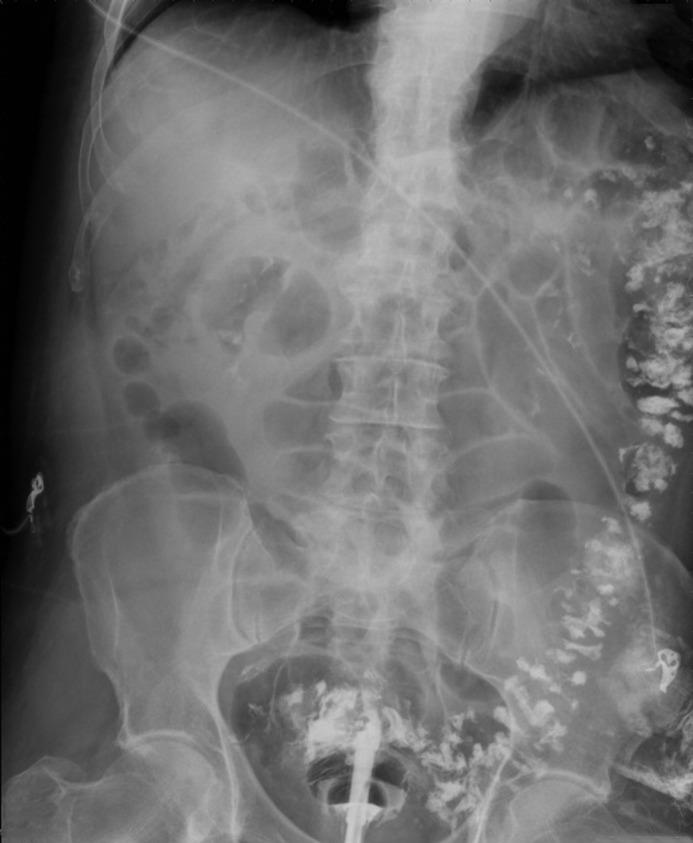

Barium Enema for Treatment for Diverticular Bleeding.

Diverticula of the colon are the most common cause of lower gastrointestinal bleeding in adults. In cases of persistent loss of blood or severe acute hemorrhage, treatment is required. However, if these modern intervention techniques are inadequate, surgical resection of the colon may be required. Diverticular bleeding often concerns patients with a high surgical risk, so a less invasive treatment is preferable. A forgotten but excellent treatment, namely that of the obsolete barium contrast enema to staunch diverticular bleeding, is the focus of this case series. We describe 3 patients who were successfully treated with barium enema.